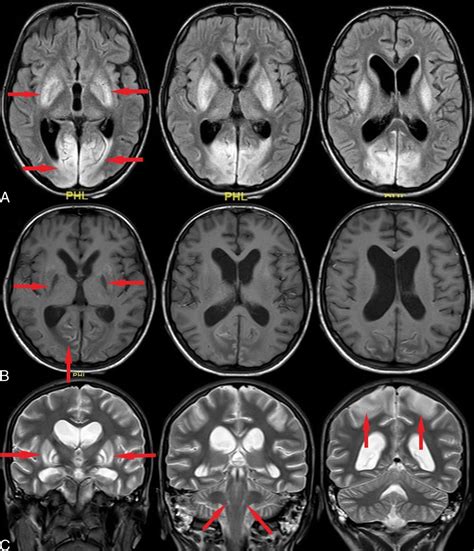

• Imaging Studies: Magnetic Resonance Imaging (MRI) or Computed Tomography (CT) scans to visualize the brain and identify any structural abnormalities.

• Neuroimaging Studies: To identify specific brain regions affected by Lance Adams Syndrome and understand how they contribute to symptoms.